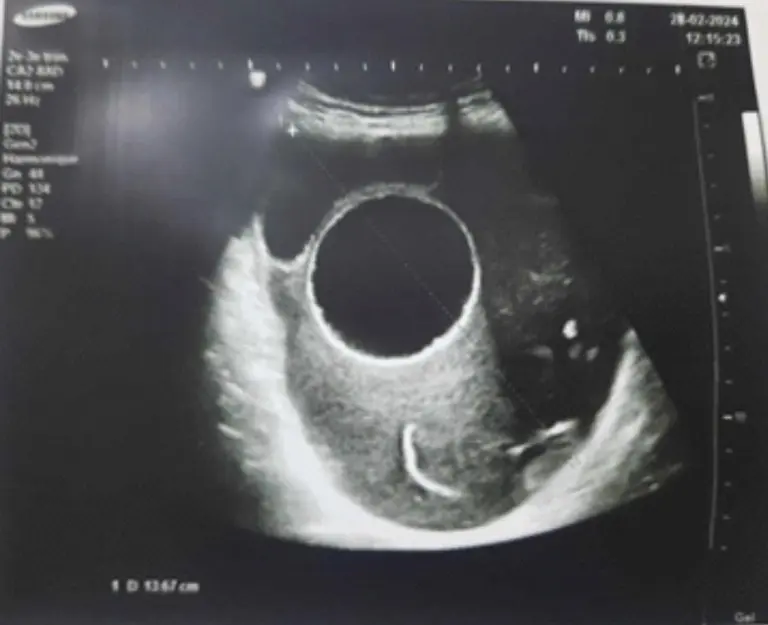

Tudjuk, hogy a kutyák nyelve a szeretet egyik nyelve – de lehet, hogy ideje „feliratozni” azt a szeretetet. Egy friss esettanulmány szerint egy 26 éves várandós nőnél egy teniszlabda méretű ciszta okozott hónapok óta tartó hasfájást – és mint kiderült, egy parazita állhatott a háttérben, amit kutyák is terjeszthetnek.

A ciszta a nő medencéjében növekedett, míg végül kórházi beavatkozásra volt szükség. Az orvosok megmentették a babát és az anyát is, majd a szövettani vizsgálat felfedte az okot: egy hidatid ciszta, azaz egy Echinococcus-fertőzés eredménye.